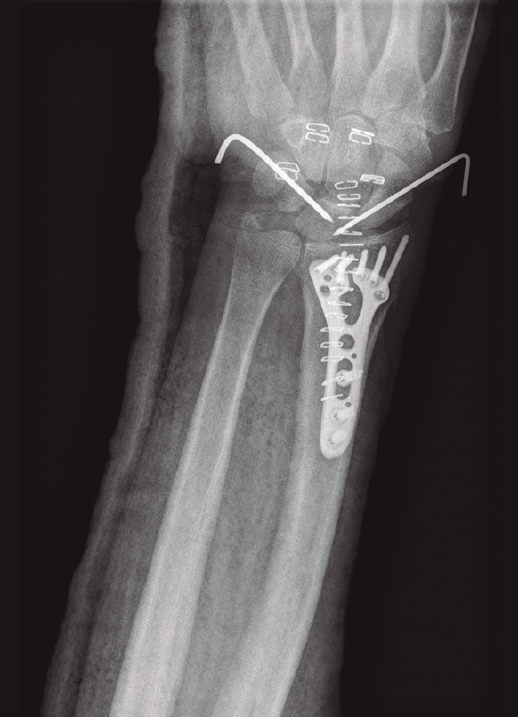

- Artroscopia de muñeca con sistema de tracción longitudinal a 10 N y vías artroscópicas estándar 3-4 y 6R para evaluar la articulación radiocarpiana y las vías mediocarpiana ulnar (MCU) y radial (MCR) en el caso de la articulación mediocarpiana, utilizando para ello una óptica de 2,3 mm y 30°(2,17), mediante técnica de artroscopia en seco(23)(Figura 2). En este tiempo quirúrgico artroscópico se evaluó: la presencia de escalón articular, la rotación de los fragmentos articulares y la existencia de lesiones asociadas al nivel del complejo del fibrocartílago articular (CFCT), así como al nivel de los ligamentos extrínsecos e intrínsecos de la muñeca(17)(Figura 3). En primer lugar, se evalúo la articulación radiocarpiana y, a continuación, la articulación mediocarpiana.

Figura 6. Fijación temporal con agujas de Kirschner intercarpianas tras observar una lesión Geissler IV de ambos ligamentos interóseos en la exploración artroscópica.